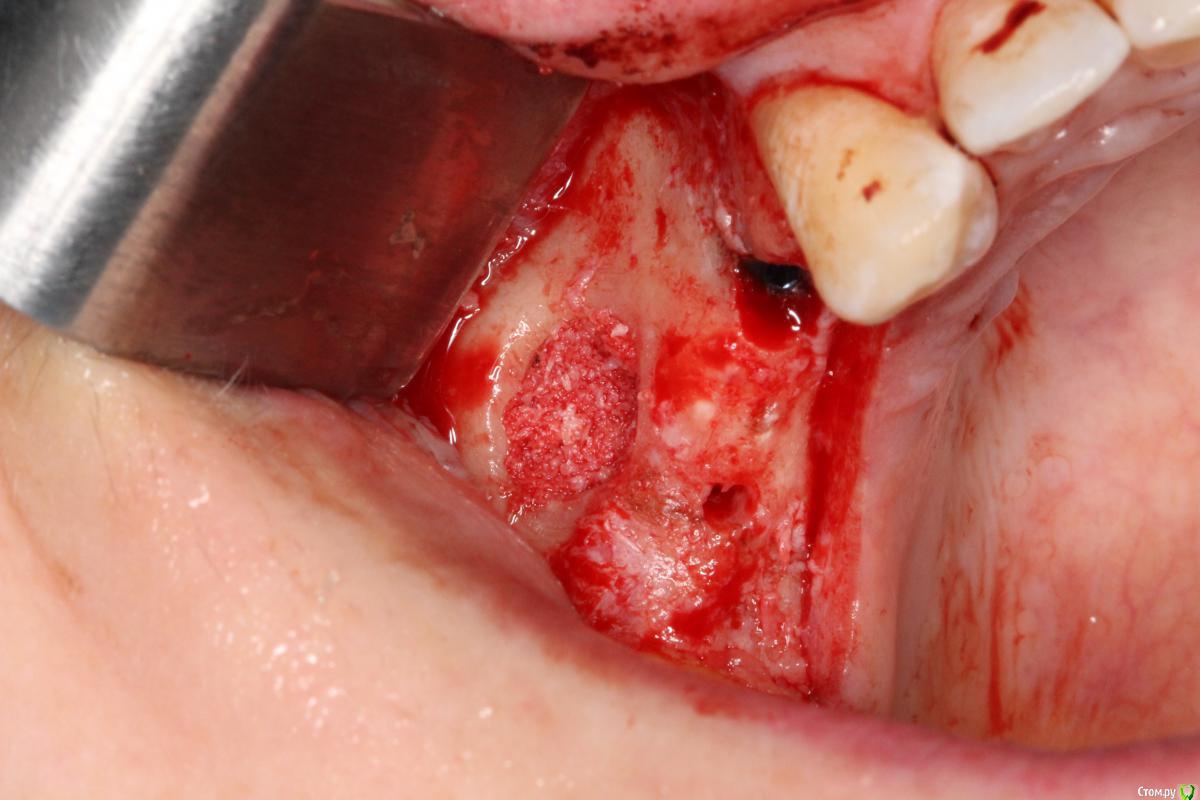

Robinbobin Опубликовано 25 марта, 2015 Поделиться Опубликовано 25 марта, 2015 Имплантаты Dio UF ll,костный материал ауто+остеоматрикс.Хотелось бы услышать мои ошибки 6 Ссылка на комментарий

Robinbobin Опубликовано 25 марта, 2015 Автор Поделиться Опубликовано 25 марта, 2015 я бы обошелся без вертикального разреза, и делал бы разрез по гребню. Почему делали открытый синус? Я делал разрез по гребню но из-за маленького опыта порвал((((Делал открытый потому что объем кости был 2-2.5 мм а боком поставить побоялся) Ссылка на комментарий

red_butler Опубликовано 25 марта, 2015 Поделиться Опубликовано 25 марта, 2015 Делал открытый потому что объем кости был 2-2.5 мм а боком поставить побоялся) все, увидел, конечно открытый Ссылка на комментарий

колесников Опубликовано 25 марта, 2015 Поделиться Опубликовано 25 марта, 2015 Вестибулярная компактная пластинка резорбируется на 3 мм у шеек имплантов. Вы конечно оставили дополнительно остеоматрикс вестибулярно ? В области 14 обязательно подсадите стт, можно на этапе формирователя. 16 можно было и короче взять,тогда бы он целиком находился в материале. А в целом Всё достойно. Ссылка на комментарий

Robinbobin Опубликовано 25 марта, 2015 Автор Поделиться Опубликовано 25 марта, 2015 Вестибулярная компактная пластинка резорбируется на 3 мм у шеек имплантов. Вы конечно оставили дополнительно остеоматрикс вестибулярно ? В области 14 обязательно подсадите стт, можно на этапе формирователя. 16 можно было и короче взять,тогда бы он целиком находился в материале. А в целом Всё достойно. Ассистент не сфографировал момент подсадки сст в область имплантата 1.4 поэтому наверно и забыл написать))) но на этапе формирователя думаю еще подсадить Спасибо! Ссылка на комментарий